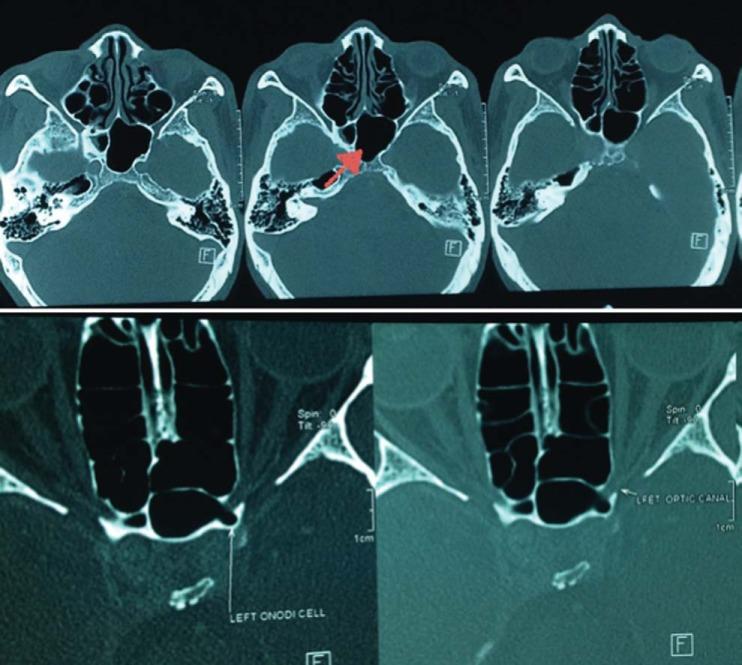

A 50 year-old gentlemen presented to the eye clinic with left eye painless loss of vision for one day. Visual acuity was counting finger in the left eye with a positive relative afferent pupillary defect (RAPD). Dilated left fundus examination revealed a pale optic disc. A computed tomography of orbit and brain showed a large left sphenoid sinus with onodi-cell-like projection on the left superior margin of left optic canal impinging on the left optic nerve. He was referred to the otorhinolaryngology team and subsequently underwent left optic nerve decompression. Post-operatively, his left visual acuity improved to 6/60 with reversal of RAPD.

一名50岁男性因左眼无痛性视力丧失一天就诊于眼科门诊。左眼视力为眼前指数,伴有相对传入性瞳孔障碍(RAPD)阳性。左眼散瞳眼底检查显示视盘苍白。眼眶和脑部计算机断层扫描显示左侧蝶窦大,左侧视神经管上缘有类似蝶筛隐窝气房的突起,压迫左侧视神经。他被转诊至耳鼻喉科团队,随后接受了左侧视神经减压术。术后,他的左眼视力提高到6/60,RAPD消失。